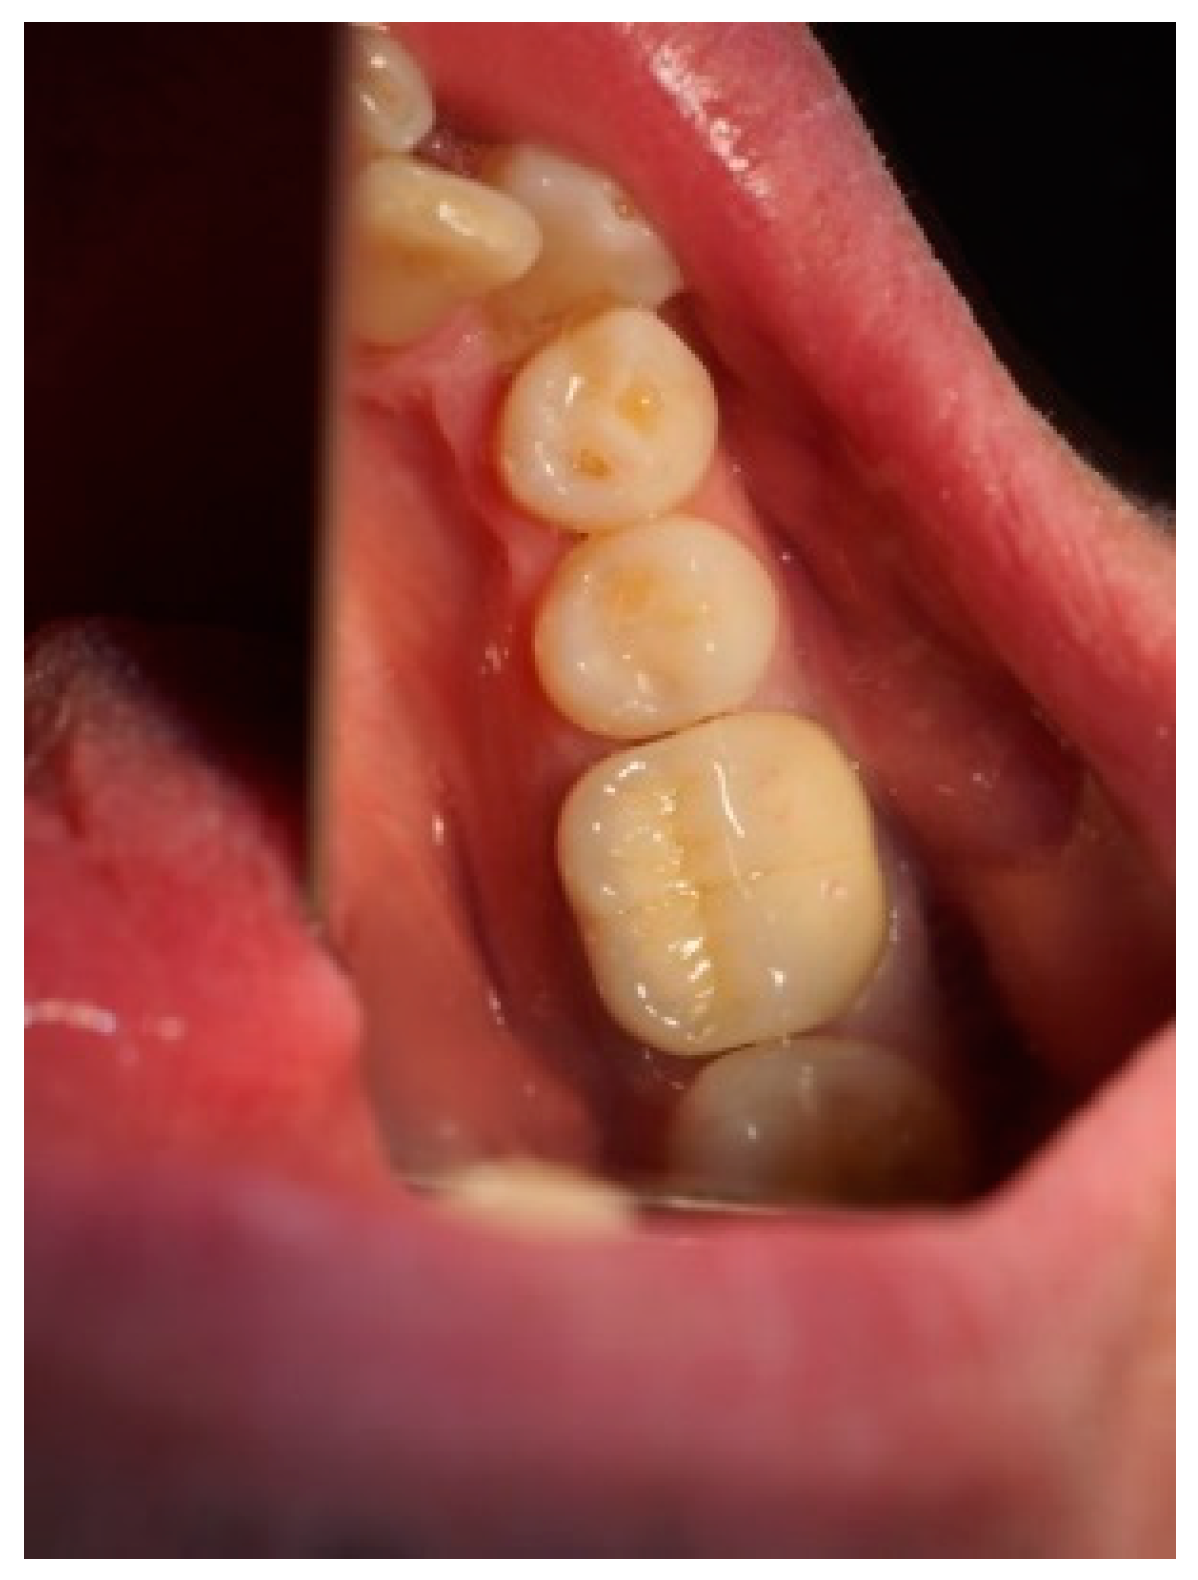

Figure 3, Figure 4, Figure 5, Figure 6, Figure 7 and Figure 8 display the follow-up of the healing process after a resective procedure for lengthening a short clinical crown with a laser.

Figure 6.

Healing in the 1st week: the wound was with a normal pale pink color, and the post and core was cemented.

Figure 7.

Healing in the 2nd week: the gingiva had a normal pale pink color.